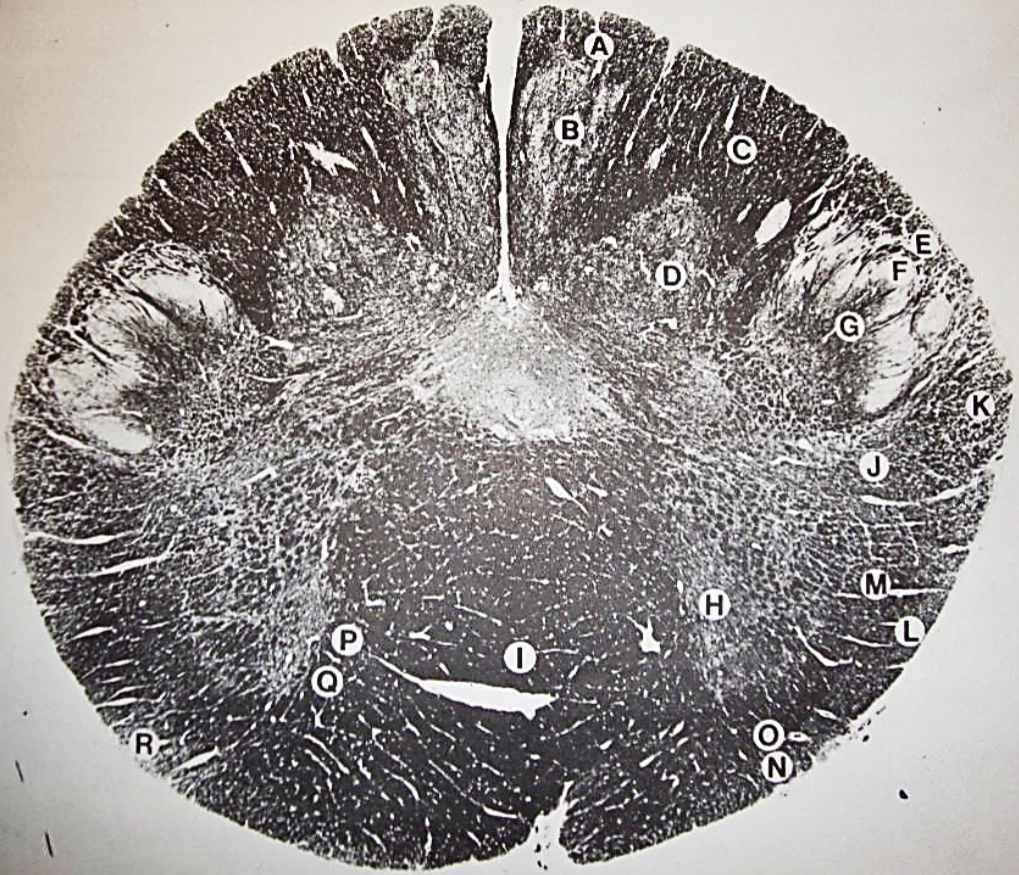

A

Fasciculus gracilis

B

gracile nucleus

C

fasciculus cuneatus

D

cuneate nucleus

E

spinal trigeminal tract

F+G collectively

spinal trigeminal nucleus

H

accessory nucleus

I

pyramidal decussation

J

rubrospinal tract

K

posterior spinocerebellar tract

L

anterior spinocerebellar tract

M

lateral spinothalamic tract

N

anterior spinothalamic tract

O

lateral vestibulospinal tract

P

medial longitudinal fasciculus

Q

tectospinal tract